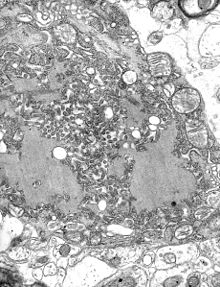

La encefalitis es un conjunto de enfermedades producidas por una inflamación del encéfalo del ser humano.[1] Son bastante frecuentes, sobre todo en determinadas regiones del mundo, y se producen generalmente por la infección de gran variedad de gérmenes como bacterias, ricketsias, espiroquetas, leptospiras, parásitos, hongos y virus. Sin embargo, con la excepción de los virus, la encefalitis suele ser un síntoma más, casi nunca el más llamativo, dentro del cuadro clínico de la enfermedad.[2] Normalmente, cuando se refiere a una encefalitis, se hace como sinónimo de encefalitis vírica.